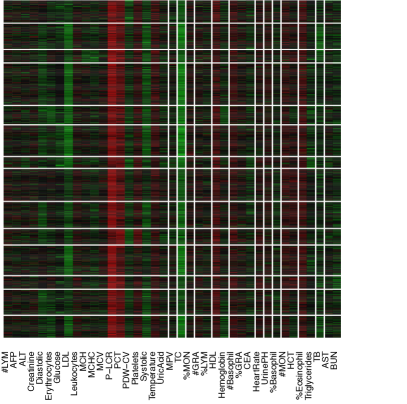

The data contain blood test results measured on 39 testing items which are listed in Table 1. Figure 1(a) shows the empirical correlation structure of the testing items as a heatmap with green, black, and red colors indicating positive, negligible and negative correlations. With appropriate ordering of the test items, one can see some patterns on the upper-left corner of the heatmap. However, the patterns seem vague and have no clear interpretation. The heatmap of the standardized data is shown in Figure 1 with green, black and red colors indicating values above, near and below the average. Next we cluster the data using a K-means algorithm with (the number of latent diseases identified in later model-based inference), applied to both, rows and columns of the data matrix. The clusters find some interesting structures. For example, indexing the submatrices in the heatmap by row and column blocks, the values in block (9,9) tend to be above the average, whereas the values in the block (1,4) tend to be below the average. However, there are at least two difficulties in interpreting the clusters as latent diseases. Firstly, there is no absolute relationship between the normal range of a testing item and its population average. A deviation from the average does not necessarily indicate an abnormality. Likewise, average values of testing items, especially those related to common diseases such as hypertension, are not necessarily within the normal range. For instance, the mean and the median of systolic blood pressure in our dataset are 147 mm Hg and 145 mm Hg, both of which are beyond the threshold 140 mm Hg for hypertension (the high blood pressure values might be related to the elderly patient population). Secondly, the exploratory analysis with K-means does not explicitly model patient-disease relationships and symptom-disease relationships. For example, one may be tempted to interpret each column block as a latent disease. As a consequence, each testing item has to be associated with exactly one disease and the patient-disease relationship is unclear. If instead, we define a latent disease by the row blocks, then each patient has to have exactly one disease and the symptom-disease relationship is ambiguous.

We can slightly improve interpretability by incorporating prior information. Specifically, each testing item comes with a reference range which we use to define symptoms: a symptom is an item beyond the reference range. In essence, we convert the original data matrix into a ternary matrix which is shown in Figure 1. The first difficulty is resolved but the second difficulty remains. For instance, the 6th column seems to suggest a disease with elevated total cholesterol and low density lipoproteins, which is also found in our later analysis with the proposed DFA. However, just as in Figure 1, it is hard to judge which blocks meaningfully represent latent disease since patient-disease relationships and symptom-disease relationships are not explicitly modeled. Besides the requirement of specifying the number of clusters, K-means is unsuitable for the task that we are pursuing in this paper.

Alternatively, instead of discretization, we can scale and center test items at the midpoint of each reference range. We show the heatmap in Figure 1 where the rows and the columns are arranged in the same way as in Figure 1. However, just as previous cases, the same limitation of interpretability still applies.